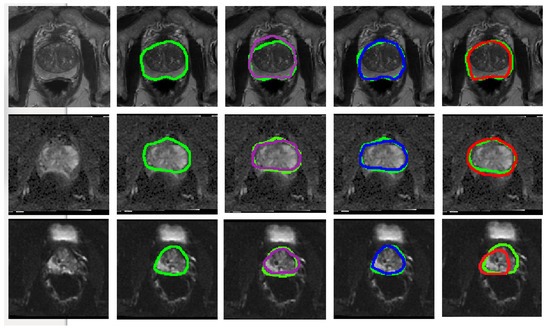

Figure 5.

Visual representation of the predicted segmentation for each model and each modality for a single slice from a case study. From the top row to the bottom: T2W, ADC and DWI. From left to right: Raw test image, Ground truth boundaries in green, U-Net’s prediction in purple, cGAN’s prediction in blue and cycleGAN prediction in red. The quantitative results show the best performance for cGAN followed by U-Net for all evaluation metrics. Scaled images are shown in Figure A1 for better visualisation.

Figure A1.

Visual representation of the predicted segmentation for each model and each modality for a single slice from a case study, where the prostate region is zoomed in and the image brightness is increased. From the top row to the bottom: T2W, ADC and DWI. From left to right: Raw test image, Ground truth boundaries in green, U-Net’s prediction in purple, cGAN’s prediction in blue and cycleGAN prediction in red. The quantitative results show the best performance for cGAN followed by U-Net for all evaluation metrics.